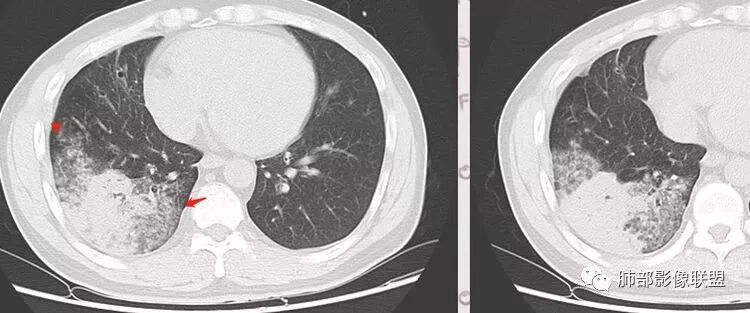

这是支气管扩张,老病灶,周围实变不明显,按理应该独立出来

下叶外基底段为主实变,周围GGO

这个病灶很有特色

分布:沿支气管段、亚段朝外蔓延分布

实变+GOG

实变区边缘收缩,支气管走形自然

但是我们也可以看到实变区很多地方没看到支气管,也就是支气管在实变区分布不均匀,提示有些地方支气管腔内有物质填塞,显示不清

GGO边界大部分不清楚,内有树芽征,中央间质均匀增厚

如果单独讨论这个病灶:我倾向于急性感染性病变

因为病灶的分布就是沿支气管走形,病灶整体就是沿段分布

实变区边界清、凹陷及平直,内部密度均匀,强化均匀,支气管在密实处填塞,其余部分通畅、走形自然,中央间质均匀增厚

GGO均匀,边界模糊,树芽征

但是问题来了:淋巴结

南边:

右肺门区淋巴结增大,融合,密度均匀,均匀强化